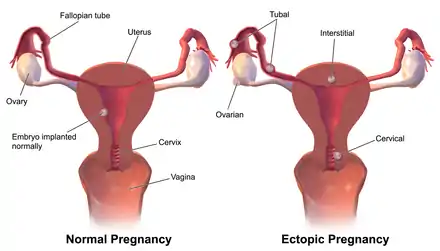

Overall, ectopic pregnancies annually affect less than 2% of pregnancies worldwide.[5] Risk factors for ectopic pregnancy include pelvic inflammatory disease, often due to chlamydia infection; tobacco smoking; prior tubal surgery; a history of infertility; and the use of assisted reproductive technology.[2] Those who have previously had an ectopic pregnancy are at much higher risk of having another one.[2] Most ectopic pregnancies (90%) occur in the fallopian tube, which are known as tubal pregnancies,[2] but implantation can also occur on the cervix, ovaries, caesarean scar, or within the abdomen.[1] Detection of ectopic pregnancy is typically by blood tests for human chorionic gonadotropin (hCG) and ultrasound.[1] This may require testing on more than one occasion.[1] Other causes of similar symptoms include: miscarriage, ovarian torsion, and acute appendicitis.[1]

The vast majority of ectopic pregnancies implant in the fallopian tube. Pregnancies can grow in the fimbrial end (5% of all ectopic pregnancies), the ampullary section (80%), the isthmus (12%), and the cornual and interstitial part of the tube (2%).[24] Mortality of a tubal pregnancy at the isthmus or within the uterus (interstitial pregnancy) is higher as there is increased vascularity that may result more likely in sudden major internal bleeding. A review published in 2010 supports the hypothesis that tubal ectopic pregnancy is caused by a combination of retention of the embryo within the fallopian tube due to impaired embryo-tubal transport and alterations in the tubal environment allowing early implantation to occur.[35]

Nontubal ectopic pregnancy

Two percent of ectopic pregnancies occur in the ovary, cervix, or are intra-abdominal. Transvaginal ultrasound examination is usually able to detect a cervical pregnancy. An ovarian pregnancy is differentiated from a tubal pregnancy by the Spiegelberg criteria.[36]